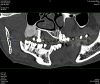

docseamew Опубликовано 6 сентября, 2013 Автор Поделиться Опубликовано 6 сентября, 2013 Уважаемые коллеги, прошу Вашей помощи еще раз. Я особо удачливый пациент, помимо вышеозначенной проблемы (стараюсь делать все как Вы посоветовали, но пока все в том же состоянии, но хоть перифокального воспаления нет), у меня есть еще вот какая беда. Одновременно с "удачным" лечением, у меня диагностирована опухоль альвеолярного отростка ВЧ. Локализуется в районе 18 удаленного зуба, размер около 20 на 24 мм, прилегает к пазухе и слегка заходит на корни 16-17 зубов. Предположительно может быть фиброзной дисплазией или еще чем похуже. Проблема у меня такая: 27 августа у меня в минском отдЧЛХ под местной анестезией взяли биопсию - просто фрезой выпилили трубчатый кусочек кости. Слизистую не резали и не ушивали, дефект затампонировали гемостатической губкой. Отправили домой и сказали мазать 3 раза в день зеленкой, обещали что через дней 10 закроется. Но не похоже, чтоб оно закрывалось. Через 3 дня отошел мацерированный кольцевидный кусочек (первоначальной отверстие было около 4 мм в диаметре. Теперь дефект слизистой составляет около 10 мм на 8 мм, несколько воспаленный край. В центре видно белое (кость с фибрином?) плюс видно трепанационное отверстие. Болевые ощущения умеренные, в основном при раздражении пищей. Скажите пожалуйста, это может закрыться? И что лучше использовать, если лечение дефекта консервативное? Ссылка на комментарий

docseamew Опубликовано 6 сентября, 2013 Автор Поделиться Опубликовано 6 сентября, 2013 Vot esche CT est u menya Ссылка на комментарий

docseamew Опубликовано 6 сентября, 2013 Автор Поделиться Опубликовано 6 сентября, 2013 vtoroi scan Ссылка на комментарий

docseamew Опубликовано 6 сентября, 2013 Автор Поделиться Опубликовано 6 сентября, 2013 i tretij scan Ссылка на комментарий

docseamew Опубликовано 6 сентября, 2013 Автор Поделиться Опубликовано 6 сентября, 2013 Извините за транслит, нет на том компьютере русской клавиатуры, и юзер я еще тот. Что с психиатра возьмешь - артист разговорного жанра...Было бы интересно узнать Ваше мнение, уважаемые коллеги, на что это похоже? А то как-то сиротливо ждать биопсии, да еще фрезевое отверстие не заживает...Заранее спасибо. Ссылка на комментарий

docseamew Опубликовано 6 сентября, 2013 Автор Поделиться Опубликовано 6 сентября, 2013 Каких-то клинических проявлений не было, никто не обращал внимания на опухоль. 18 зуб располагался практически горизонтально и был удален 2 года назад после развития пульпита. Удалился очень легко. Слизистая над опухолью была не измененная (до биопсии). Вот такой анамнез. Ссылка на комментарий